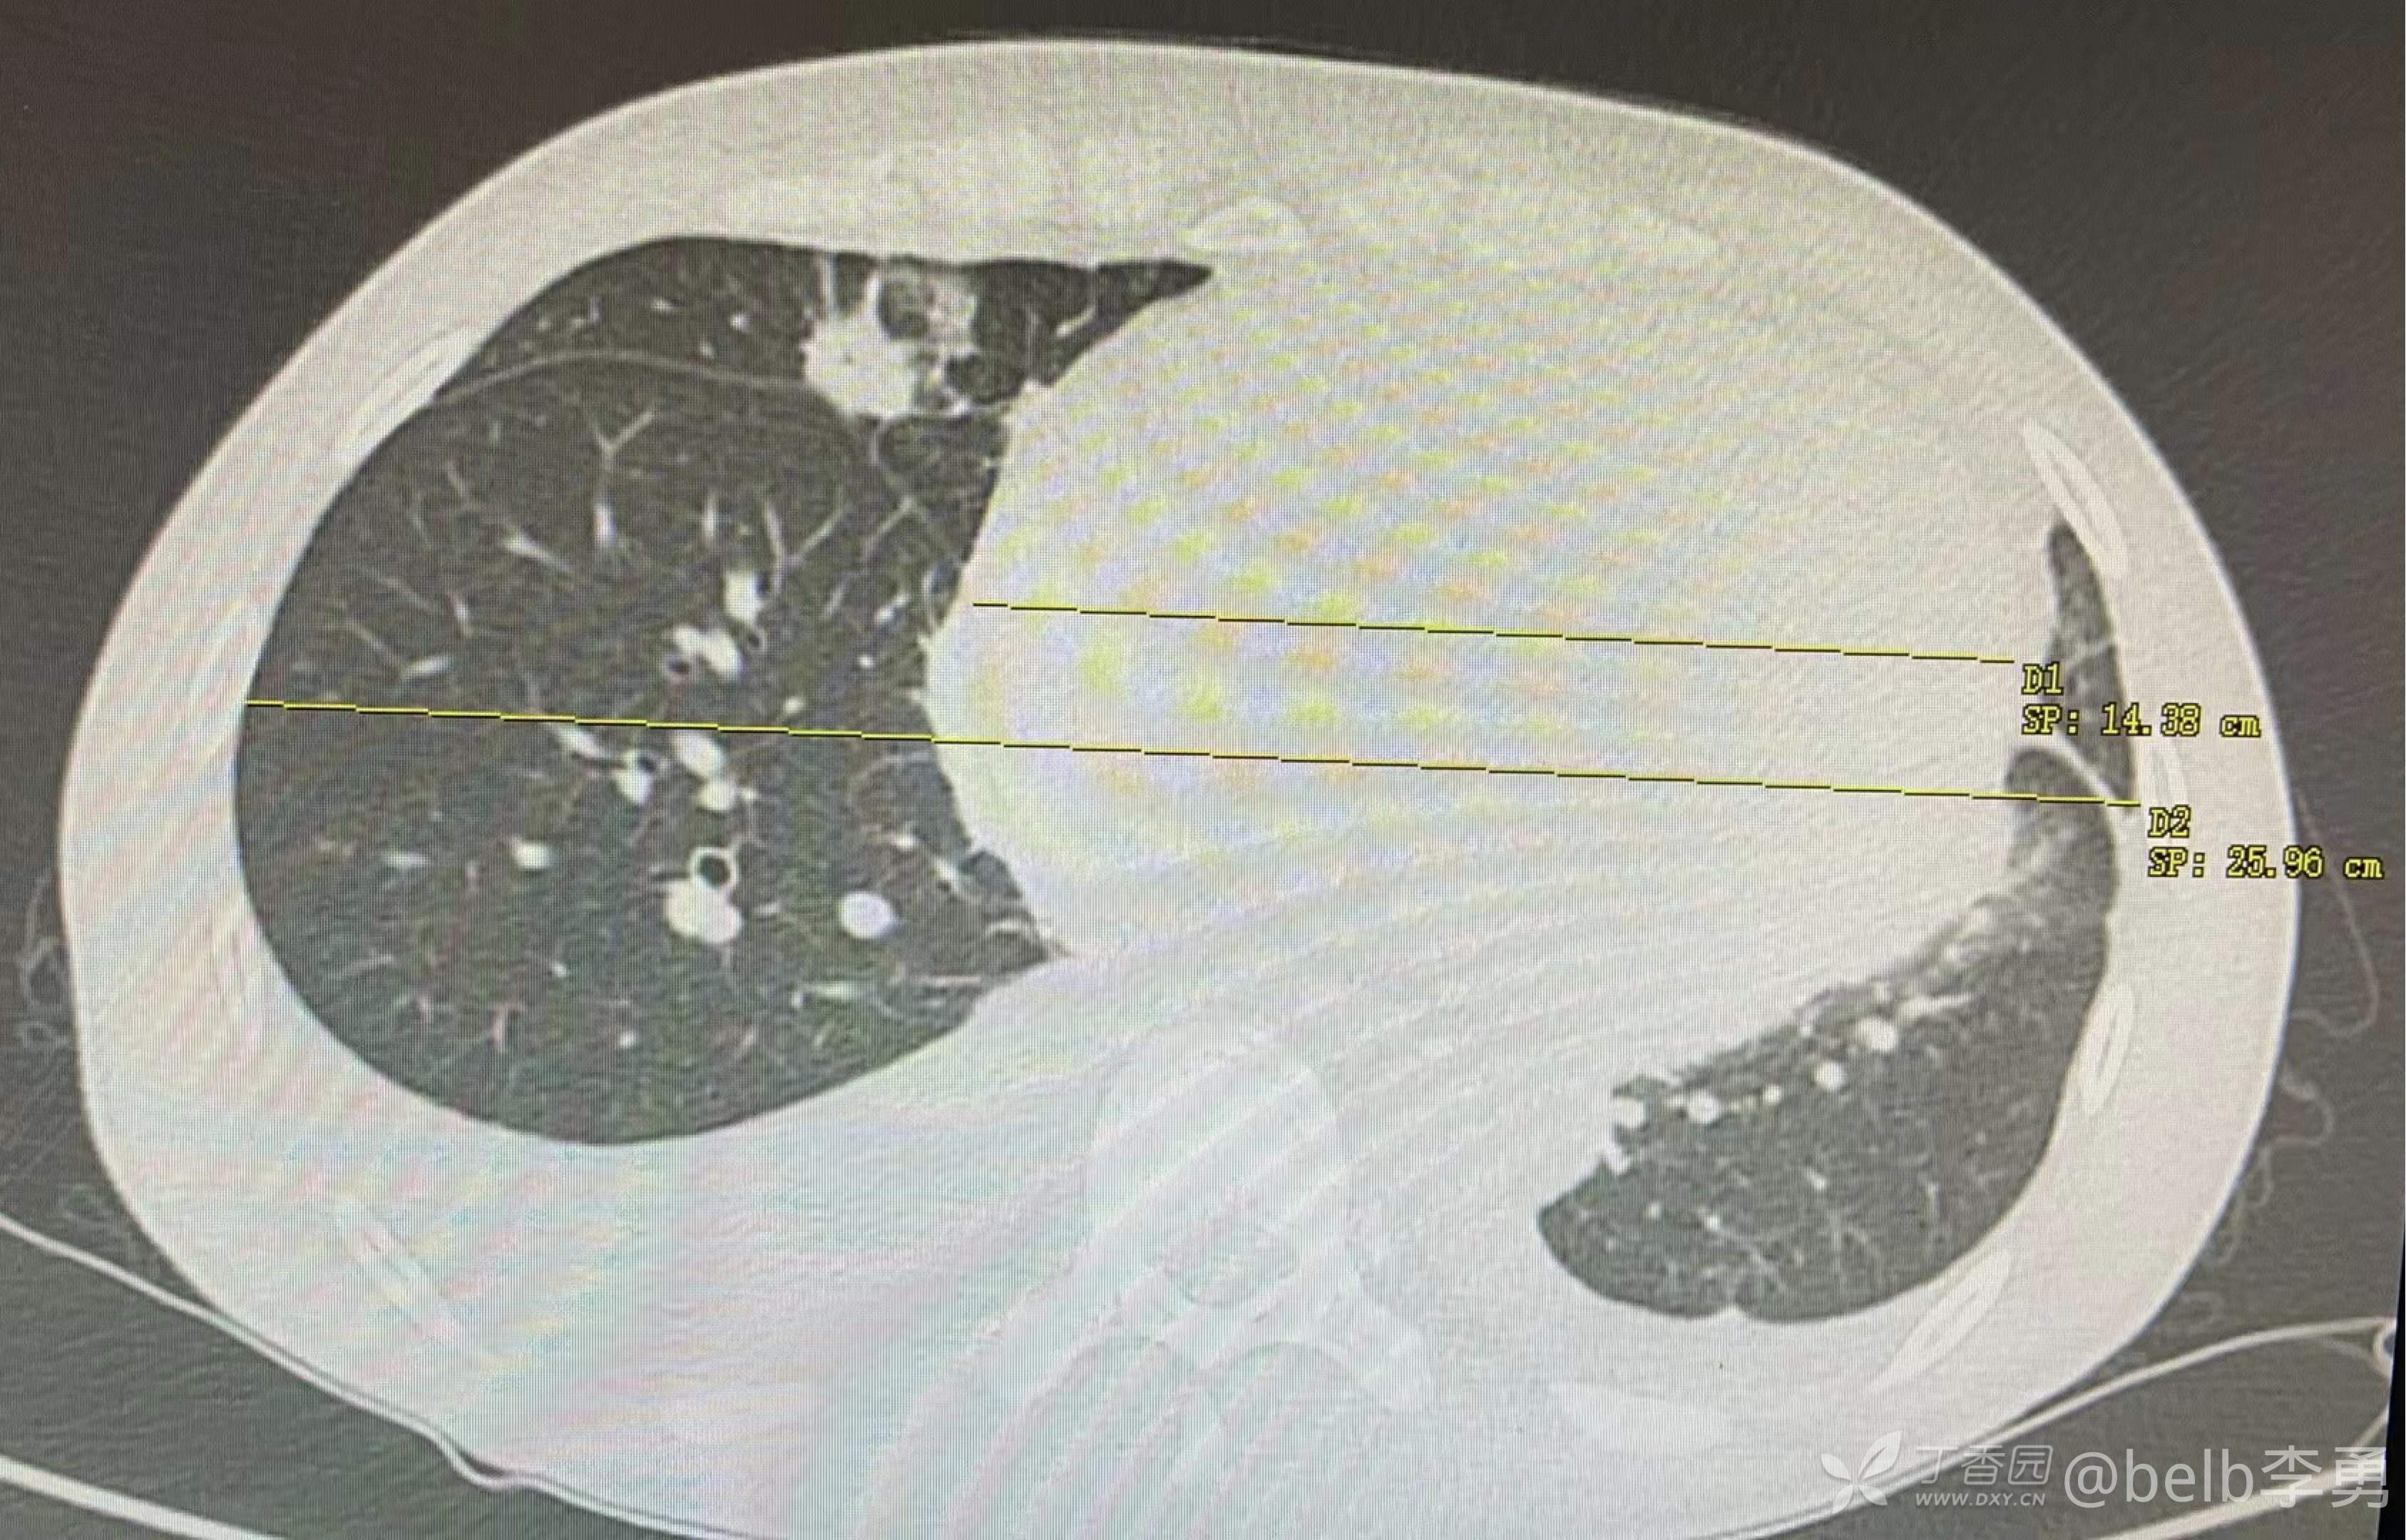

CT示双侧胸腔积液,右侧为多,右肺中叶炎症,似为空洞。